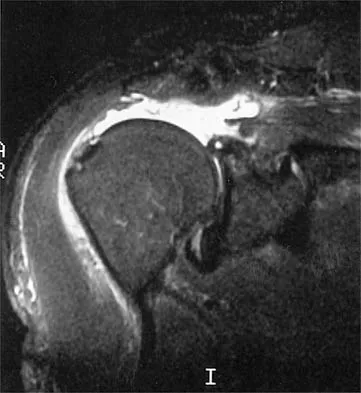

A 47-year-old male tennis player has pain in his nondominant shoulder that has failed to respond to 4 months of nonsurgical management. Examination reveals acromial tenderness and pain at the supraspinatus tendon insertion. He has a positive impingement sign, pain on forward elevation, and minimal cuff weakness. The MRI scans are shown in Figures 30a and 30b. To completely resolve his symptoms, treatment should consist of